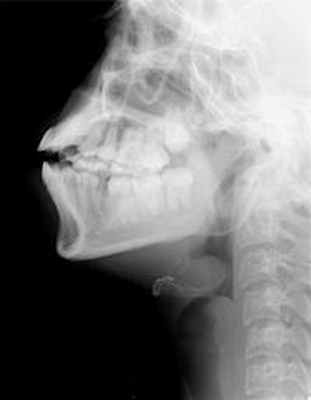

Больной С., 34 года, в октябре 2016 г. бригадой скорой медицинской помощи был доставлен в ЛОР-отделение ГБУЗ МО МОНИКИ им. М.Ф. Владимирского с резаной раной шеи.

В момент поступления состояние пациента крайне тяжелое, что было обусловлено нестабильной гемодинамикой (пульс 75—120 в 1 мин, АД 80/60 мм рт.ст.), нарушением дыхания (выраженная одышка — ЧДД 30—35 в 1 мин, цианоз кожных покровов), выраженным возбужденным состоянием. На шее повязка, через которую отмечается умеренное кровотечение.

Диагноз при поступлении: резаная рана шеи с повреждением ротоглотки и сосудов шеи.

На основании диагноза определены показания к срочной ревизии и первичной хирургической обработке раны. Протокол хирургического вмешательства: в связи с невозможностью оротрахеальной интубации операция выполнена под внутренней анестезией. Выявлено полное пересечение мышц надподъязычной группы непосредственно выше подъязычной кости; отмечается зияющий дефект глотки, через который видна ее задняя стенка, подъязычная кость вместе с гортанью смещена вниз, язык отсечен от основания и западает кзади, что вызывает нарушения дыхания и создает угрозу асфиксии, препятствует выполнению оротрахеальной интубации. Расхождение краев раны составляет 1,5—2 см. В ране отмечается выраженное кровотечение и скопление слюны. Источником массивного кровотечения является пересеченная правая верхнещитовидная артерия. Поврежденная артерия взята на зажим, а затем перевязана. Подъязычная кость и надгортанник взяты на зажимы, гортань подтянута кверху, после чего проведена временная интубация трахеи через рану. Через дополнительный разрез на уровне второго—третьего колец трахеи наложена трахеостома, после чего в трахею введена интубационная трубка с манжетой (рис. 1). Рис. 1. Больной С. Интубация трахеи через наложенную трахеостому. Из глотки и полости рта удалено большое количество крови и сгустков, после чего введен назогастральный зонд. Визуализируются три резаные раны корня языка, которые были последовательно ушиты. Выявлено повреждение правой подчелюстной железы, а в латеральном углу раны определяется наружная сонная артерия (рис. 2). Рис. 2. Первичная хирургическая обработка раны. Описание в тексте.

После тщательного гемостаза в рану введены резиновые выпускники, наложены послойные швы. В трахеостому установлена трахеостомическая трубка с манжетой фирмы Pentax № 8 (рис. 3). Рис. 3. Больной С. Послеоперационная рана на шее с установленными дренажами. Асептическая повязка.

Послеоперационный период протекал гладко. Трахеостомическая трубка удалена на 7-е сутки, дыхание свободное. Назогастральный зонд удален на 10-е сутки. Рана зажила первичным натяжением. Больной выписан в удовлетворительном состоянии на 14-е сутки после операции. В отдаленном периоде (через 3 мес) проведен осмотр: на передней поверхности шеи послеоперационный линейный рубец и в типичном месте рубец после трахеостомии, признаков стеноза глотки, гортани и трахеи не обнаружено (рис. 4). Рис. 4. Больной С. через 3 мес после операции.

Особенности данного наблюдения заключаются в обширном ранении полых органов шеи и прилегающих анатомических структур, что препятствовало выполнению традиционной оротрахеальной интубации и потребовало индивидуального подхода к выбору адекватного способа анестезии, обеспечившей возможность своевременного выполнения одноэтапного хирургического вмешательства в необходимом объеме и выздоровление больного.